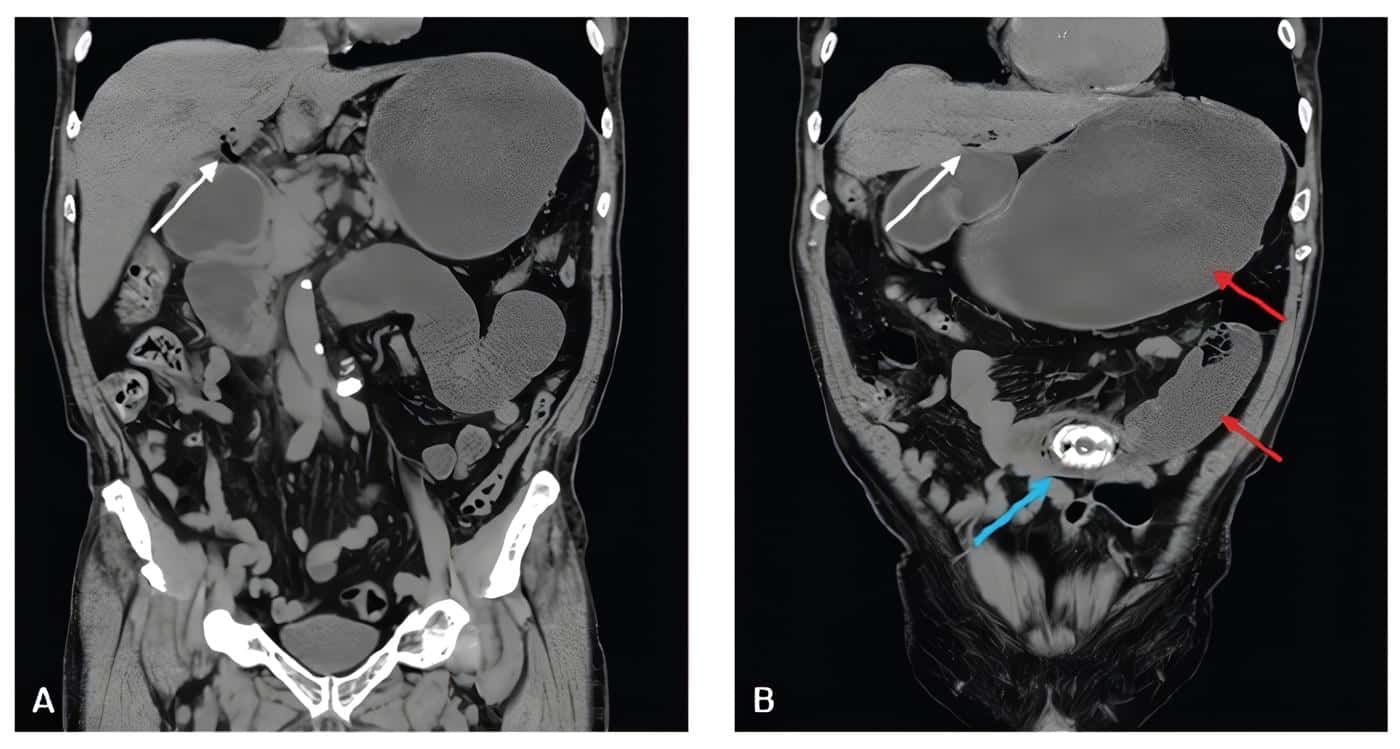

Se manejó con cristaloides y antiespasmódico en urgencias, pensando en cuadro de urolitiasis. La urotomografía descartó cálculos en las vías urinarias, pero evidenció imagen hiperdensa intraluminal a nivel de intestino delgado, además neumobilia y fistula colecisto entérica (Figura 2).

Figura 2. Tomografía abdominal simple en corte coronal. A: neumobilia (flecha blanca). B: Triada de Rigler, con neumobilia (flecha blanca), dilatación de asas intestinales (flechas rojas) y calculo biliar obstructivo (flecha azul). Fuente: los autores.

En los dos casos presentados, el diagnóstico se hizo mediante tomografía abdominal simple, en la cual se observó el lito a nivel de intestino delgado, además de la triada de Rigler.